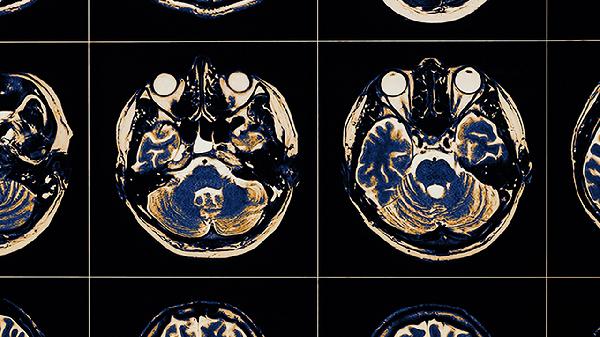

脑血栓症状主要包括肢体无力、言语不清、头晕头痛、视力障碍和意识障碍。脑血栓是由于脑血管内血栓形成导致脑组织缺血缺氧引起的,可能与动脉粥样硬化、高血压、糖尿病等因素有关,通常表现为突发性神经功能缺损。

后循环脑血栓常引发眩晕、平衡障碍或剧烈头痛,与椎基底动脉系统缺血有关。患者可能出现视物旋转、恶心呕吐,严重时出现共济失调。急性期可静脉滴注银杏达莫注射液改善微循环,配合盐酸氟桂利嗪胶囊缓解血管痉挛,同时需监测血压变化。

脑血栓可能导致短暂性黑矇、视野缺损或复视,与枕叶或脑干缺血相关。部分患者出现瞳孔不等大、对光反射迟钝等体征。治疗需及时进行头颅影像学检查,根据病情选用注射用尤瑞克林扩张血管,配合甲钴胺片营养视神经。